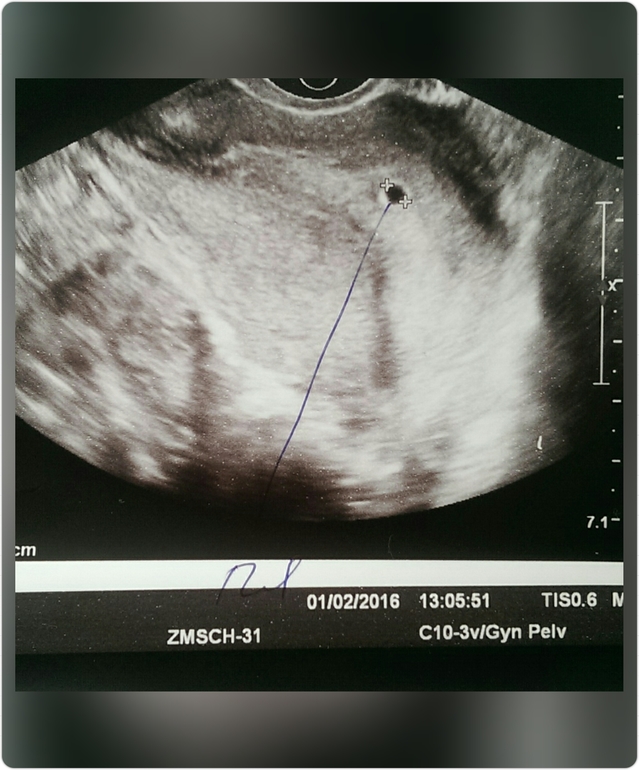

Нам сегодня 5 недель и 1 день ... 👼

Врачи выписывают, так как нашли ПЯ )) размер правда не сказали, но ЖТ уменьшилось ... Неделю назад было 19мм, сегодня 17мм ... Хм... Будем поддерживать ...

Выписывают со спойоной душой! Через неделю контроль узи, что бы услышать сердечко! Наше с мужем сердечко!!! 💖